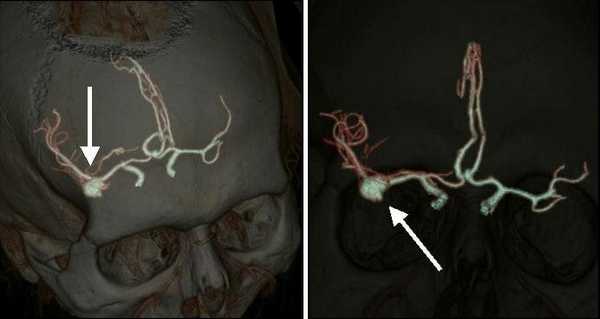

КТ-ангиография головного мозга (3D-реконструкция). Аневризматическое расширение левой средней мозговой артерии

· Компьютерная томография - ангиография головного мозгаявляется наиболее достоверным неинвазивным методом диагностики аневризм сосудов головного мозга.На КТА выявляются признаки аневризмы сосудов головного мозгав виде локального выпячивания стенки артерии.

· Магнитно-резонансная томография головного мозга выявляет характерную картину мешотчатого образования в проекции сосудов головного мозга.Магнитно-резонансная томография головного мозга в артериальном режиме выявляет локальное выпячивание стенки церебрального сосуда.

· Церебральная ангиография является наиболее достоверным, инвазивным методом диагностики аневризм сосудов головного мозга. На церебральной ангиографии определяется локальное выпячивание стенки артерии головного мозга.